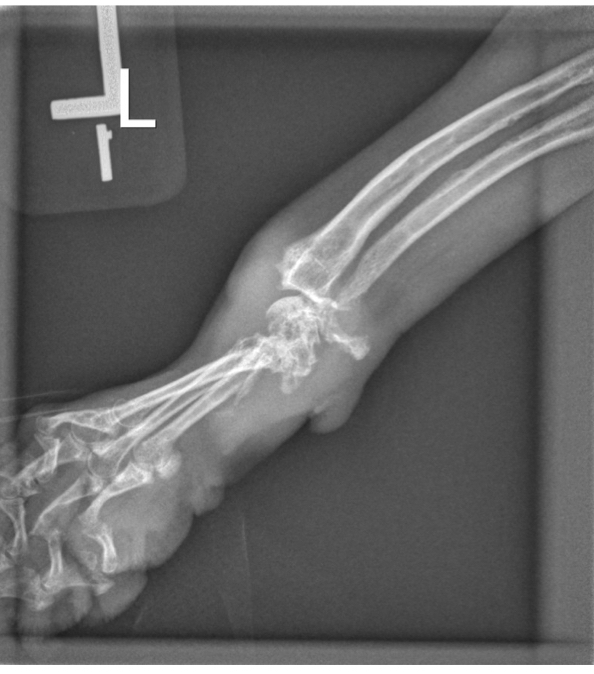

Q

What wrong

lytic lesions in carpus